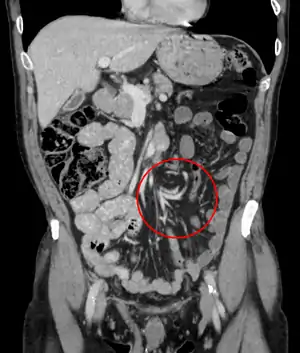

Volvulus

Coronal CT of the abdomen, demonstrating a volvulus as indicated by twisting of the bowel stock